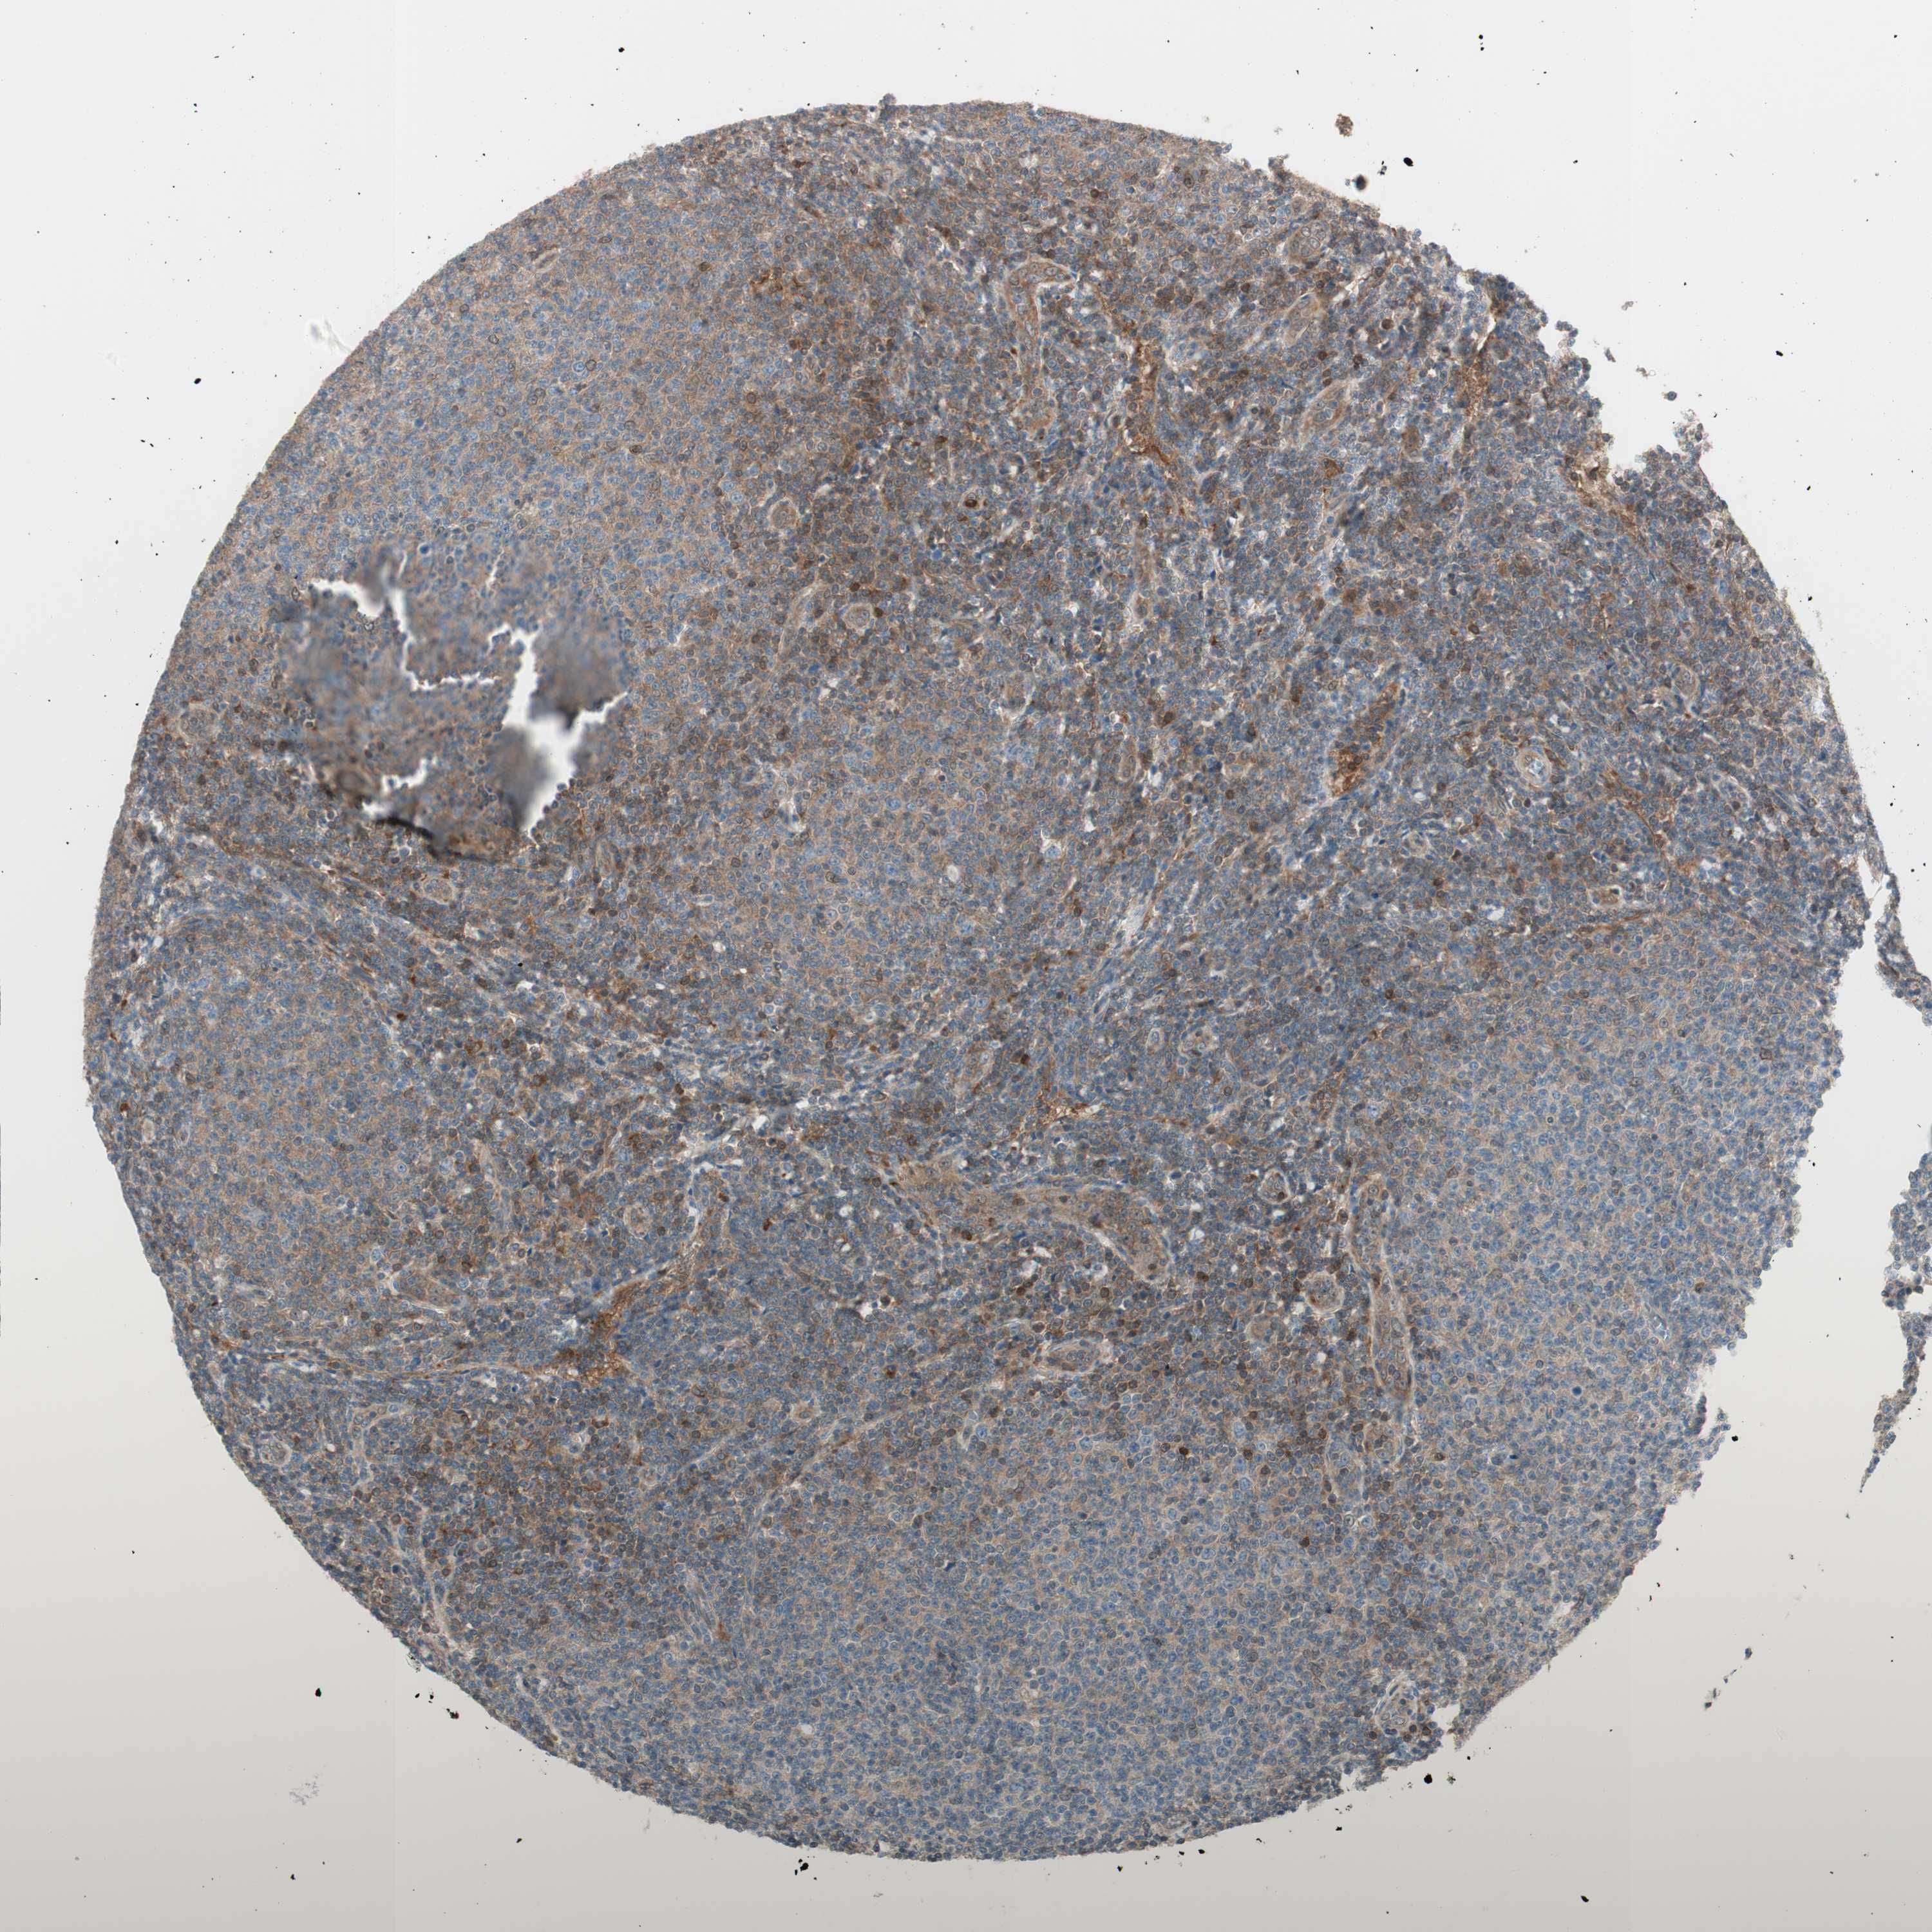

LYMPHOMA - Protein expressioni

A mouse-over function shows sample information and annotation data. Click on an image to view it in a full screen mode. Samples can be filtered based on level of antibody staining by selecting one or several of the following categories: high, medium, low and not detected. The assay and annotation is described here.

Antibody stainingi

Antibody staining in the annotated cell types in the current human tissue is reported as not detected, low, medium, or high, based on conventional immunohistochemistry profiling in selected tissues. This score is based on the combination of the staining intensity and fraction of stained cells.

Each image is clickable and will lead to virtual microscopy that enables deeper exploration of all samples and also displays staining intensity scores, fraction scores and subcellular localization as well as patient and tissue information for each sample.

Antibody HPA004868

Antibody HPA005729

Staining

High

Medium

Low

Not detected

Intensity

Strong

Moderate

Weak

Negative

Quantity

>75%

75%-25%

<25%

None

Location

Nuclear

Cytoplasmic/membranous

Cytoplasmic/membranous,nuclear

Malignant lymphoma, non-Hodgkin's type, Low grade

Malignant lymphoma, non-Hodgkin's type, High grade